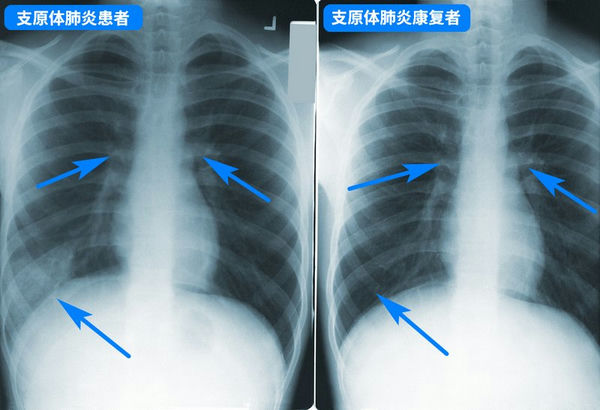

支原體肺炎胸透片

支原體肺炎***般并不嚴(yán)重,但要小心預(yù)防病情加重,盡早就醫(yī),如持續(xù)發(fā)燒5天以上、劇烈咳嗽不止,則***定要就醫(yī),以評(píng)估肺部是否受影響,以及是否存在并發(fā)癥。兒童支原體肺炎***般用阿奇霉素等大環(huán)內(nèi)酯類藥物,但因?yàn)閬喼薜貐^(qū)濫用藥物引起的耐藥性問題,很可能效果不佳,需要中途換藥,具體應(yīng)該遵醫(yī)囑。